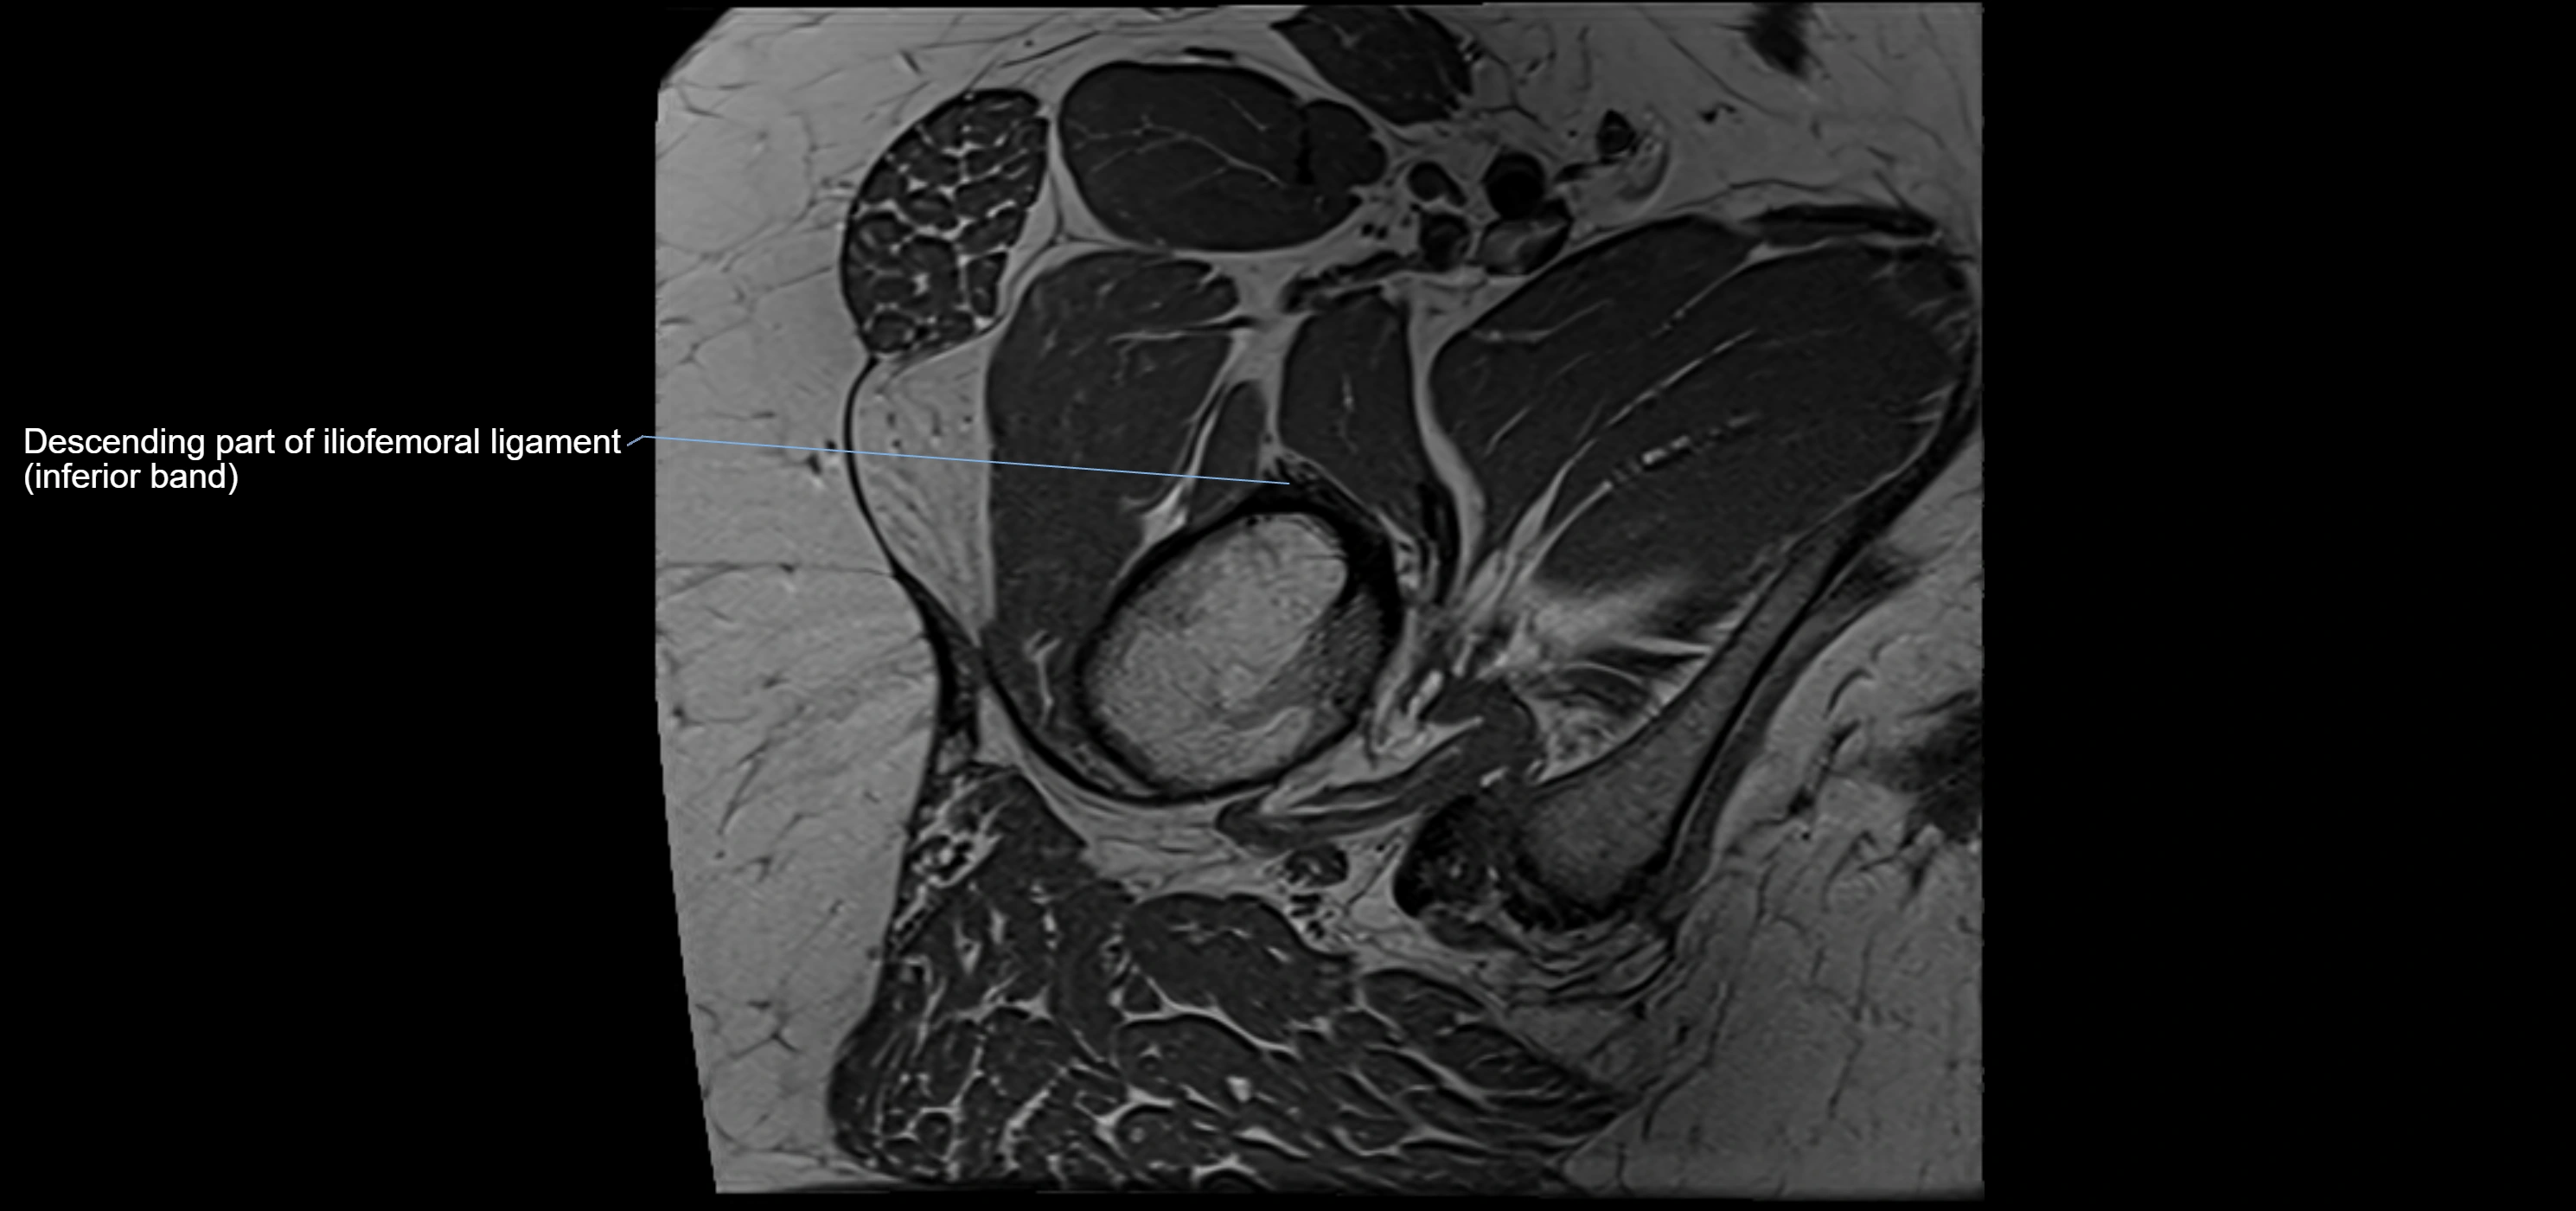

MRI Appearance

T1-weighted images:

• Labrum: low signal intensity (dark)

• Surrounded by intermediate signal joint fluid (bright on arthrogram)

• Tears: linear or focal areas of intermediate-to-high signal interrupting labral continuity

T2-weighted images:

• Joint fluid: bright, making labral tears visible as fluid extending into or around labrum

• Degeneration: may show areas of increased signal within labrum

MRI image

image